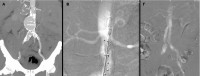

Με επιτυχία πραγματοποιήθηκε, για πρώτη φορά στην Ελλάδα, στο Ιατρικό Κέντρο Αθηνών, η διαδερμική ενδαγγειακή αποκατάσταση κοιλιακού ανευρύσματος μόνο με τη χρήση διοξειδίου του άνθρακα (CO2) και χωρίς καθόλου ιωδιούχο σκιαγραφικό. Η νέα, καινοτόμος τεχνική εφαρμόστηκε από την αγγειοχειρουργική ομάδα του κ. Θεοδόσιου Μπίσδα, MD, PhD, Αναπληρωτή Καθηγητή Αγγειοχειρουργικής στην Πανεπιστημιακή Κλινική Muenster Γερμανίας, Ενδοαγγειακό Χειρουργό, Φλεβολόγο, Κλινική Αγγειακής και Ενδοαγγειακής Χειρουργικής.Η ενδαγγειακή αντιμετώπιση αορτικών ανευρυσμάτων έχει αντικαταστήσει, σχεδόν πλήρως, την ανοιχτή χειρουργική εξαιτίας της ελάχιστης επεμβατικότητας της μεθόδου, της γρήγορης ανάρρωσης του ασθενούς και της ασφάλειας των σύγχρονων μοσχευμάτων. Η τεχνική απαιτεί όμως, τη χρήση ιωδιούχου σκιαγραφικού, στο πλαίσιο της αγγειογραφίας, για την απεικόνιση των αγγείων πριν και μετά την τοποθέτηση των μοσχευμάτων. Η ποσότητα του σκιαγραφικού που χρησιμοποιείται είναι ανάλογη της πολυπλοκότητας του ανευρύσματος. Επιπρόσθετα, ο ασθενής λαμβάνει επιπλέον ιωδιούχο σκιαγραφικό κατά τη διάρκεια της αξονικής αγγειογραφίας που είναι απαραίτητη πριν την επέμβαση αλλά και μετεγχειρητικά, ιδιαίτερα σε πολύπλοκα αορτικά ανευρύσματα.

Αξίζει να σημειωθεί ότι η ποιότητα της αγγειογραφίας ήταν ισάξια με αυτήν του ιωδιούχου σκιαγραφικού, τα μοσχεύματα τοποθετήθηκαν με απόλυτη επιτυχία αποκλείοντας το ανεύρυσμα και η νεφρική λειτουργία του νεφροπαθούς ασθενούς δεν επηρεάστηκε καθόλου.